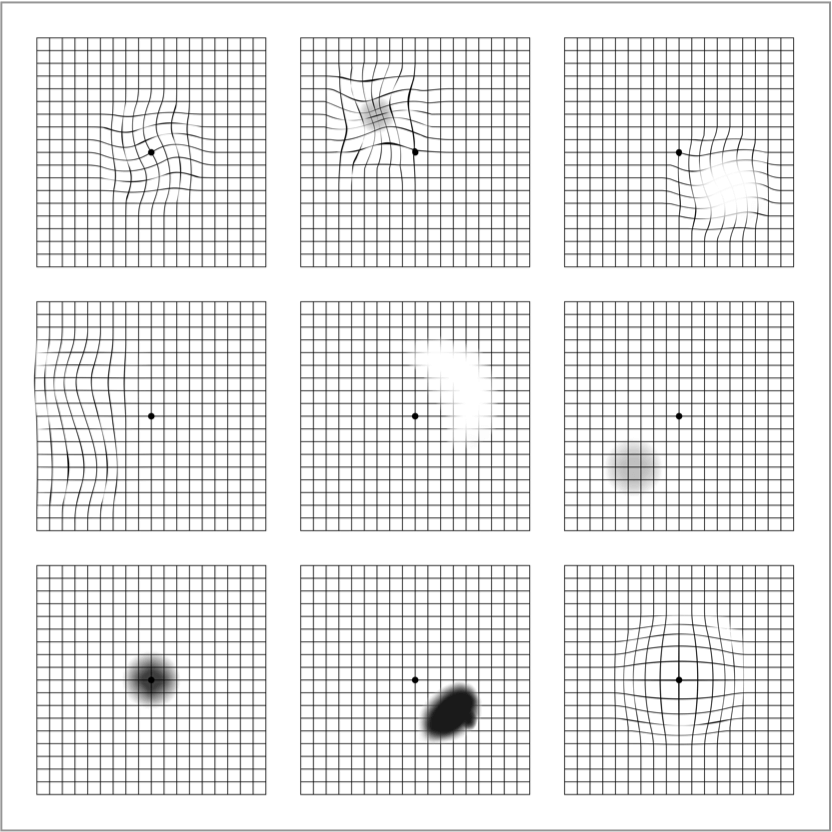

Uma grade de Amsler é uma ferramenta simples e essencial de automonitoramento, usada para detectar alterações precoces na visão. Isso pode incluir distorção (linhas retas que parecem onduladas), manchas embaçadas ou manchas escuras.3

É importante não usar a grade de Amsler para fins de diagnóstico; ela não substitui os exames regulares dos olhos. A única maneira de diagnosticar a DMRI ou AG é por meio de um exame completo do olho, incluindo uma verificação da mácula, feito por um oftalmologista ou optometrista

Lembre-se que alterações na visão em uma grade de Amsler podem indicar uma doença ocular diferente de DMRI ou AG.

Se você detectar qualquer alteração na sua visão, é importante conversar com um oftalmologista ou optometrista o mais rápido possível.